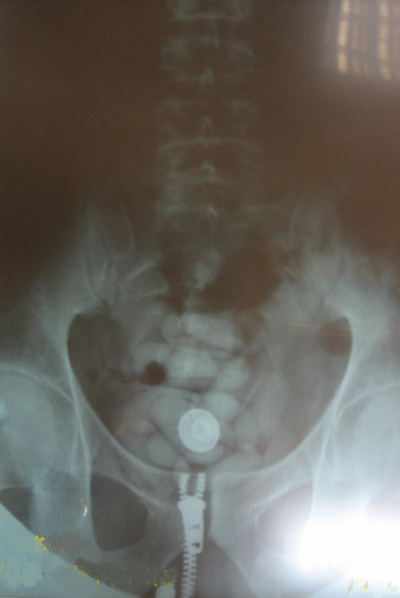

A los policías de la comisaría de Barajas les basta con echar una ojeada a los pasajeros de cualquier vuelo caliente -sobre todo, los procedentes de Sudamérica- para detectar a quienes vienen cargados de droga. "En cada vuelo seleccionamos de forma aleatoria a entre 15 y 30 pasajeros", explica el inspector. "Les sometemos a una entrevista y, al final, nos quedamos con cuatro o cinco que nos parecen sospechosos. Les hacemos pasar por los rayos X..., y casi nunca nos equivocamos. Lo más probable es que alguno de ellos vaya cargado de pelotas de cocaína... O si no, que lleven una faja con droga o un doble fondo en la maleta".

Hace poco, los agentes sospecharon de una joven. Le hicieron apartarse de la fila del control de pasaportes y le explicaron por qué: "Creemos que lleva usted droga y le vamos a hacer una radiografía". Ella replicó con un mohín y alegó que estaba embarazada. Creía que así podría eludir el examen radiológico. Pero los policías le sacaron de su error y le explicaron que en ese supuesto iría detenida hasta un hospital, donde se le sometería a una exploración ginecológica. Al final, la mula se rindió y aceptó que le hicieran una placa de rayos X. Ocultaba decenas de cápsulas de cocaína dentro del vientre.